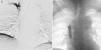

Dados los hallazgos radiológicos y al confirmarse la sospecha diagnóstica, se decidió iniciar tratamiento fibrinolítico urgente vía cefálica derecha y basílica izquierda (fig. 1A) con uroquinasa a dosis de 250.000 unidades en bolo, seguidas de 120.000 unidades por hora, que se prolonga durante 48h ante la presencia de restos de trombo en el primer control.

La flebografía de control mostró permeabilidad de ambos troncos y de vena cava superior, evidenciándose además estenosis focal de la misma a la altura del extremo distal del catéter reservorio. En vista de los hallazgos, se llevó a cabo angioplastia simple de vena cava superior con buen resultado angiográfico (fig. 1B). El paciente presentó evolución favorable tras el procedimiento con resolución completa de sus síntomas. Dos días después de la fibrinólisis se procedió a la retirada del catéter venoso yugular derecho y reservorio subcutáneo.